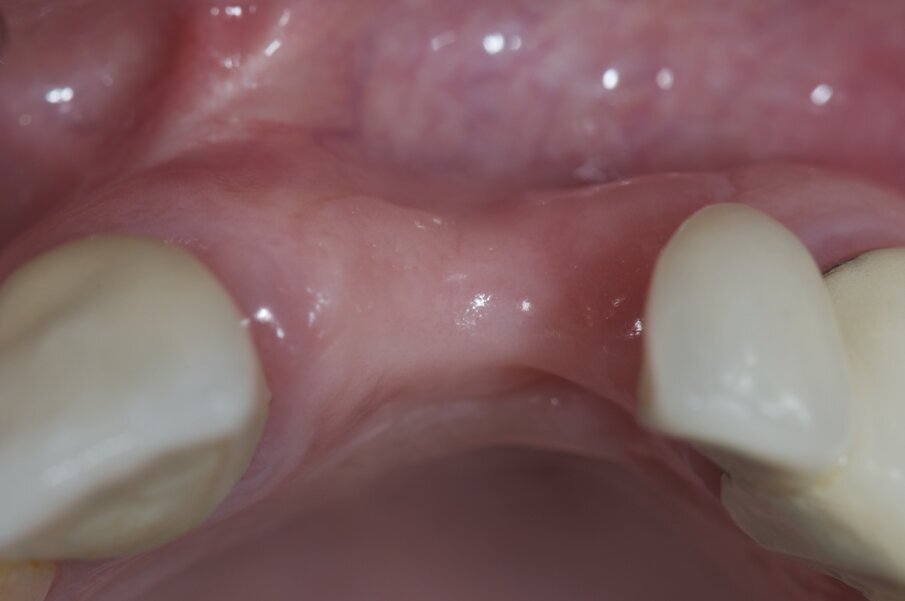

I risultati della guarigione a 9 mesi (Figg. 13, 15).

Fig. 14 - Valutazione sito rigenerato in visione frontale.

Fig. 15 - Valutazione sito rigenerato in visione occlusale.

Fig. 20 - Scopertura degli impianti.